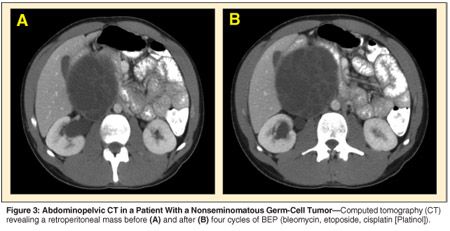

A 21-year-old man presented with right testicular pain and discomfort referable to a palpable right-sided lower abdominal mass. Right radical orchiectomy revealed a 2-cm nonseminomatous germ-cell tumor comprised of embryonal carcinoma and mature teratoma. Abdominal computed tomography (CT) showed a large multiloculated mass with solid and cystic components in the right retroperitoneum. AFP and HCG were elevated at 1,700 ng/mL and 150 mIU/mL, respectively. Four cycles of BEP chemotherapy were administered, with normalization of serum tumor markers. A repeat CT of the abdomen and pelvis revealed a 5-mm increase in the size of the large retroperitoneal mass (see Figure 3). The patient was also found to have deep-venous thrombosis extending from the iliac vessels into the vena cava.

The patient underwent resection of massive retroperitoneal tumor with bilateral retroperitoneal lymph node dissection, vena caval tumor embolectomy, and resection of the right common iliac vein (see Figures 4 and 5). Pathology revealed a 21 × 19 cm, 1,400-g, mature teratoma with cystic differentiation. No residual malignancy was detected in the RPLND specimen. Serum HCG normalized postoperatively. The patient remains without evidence of disease 10 months postoperatively.